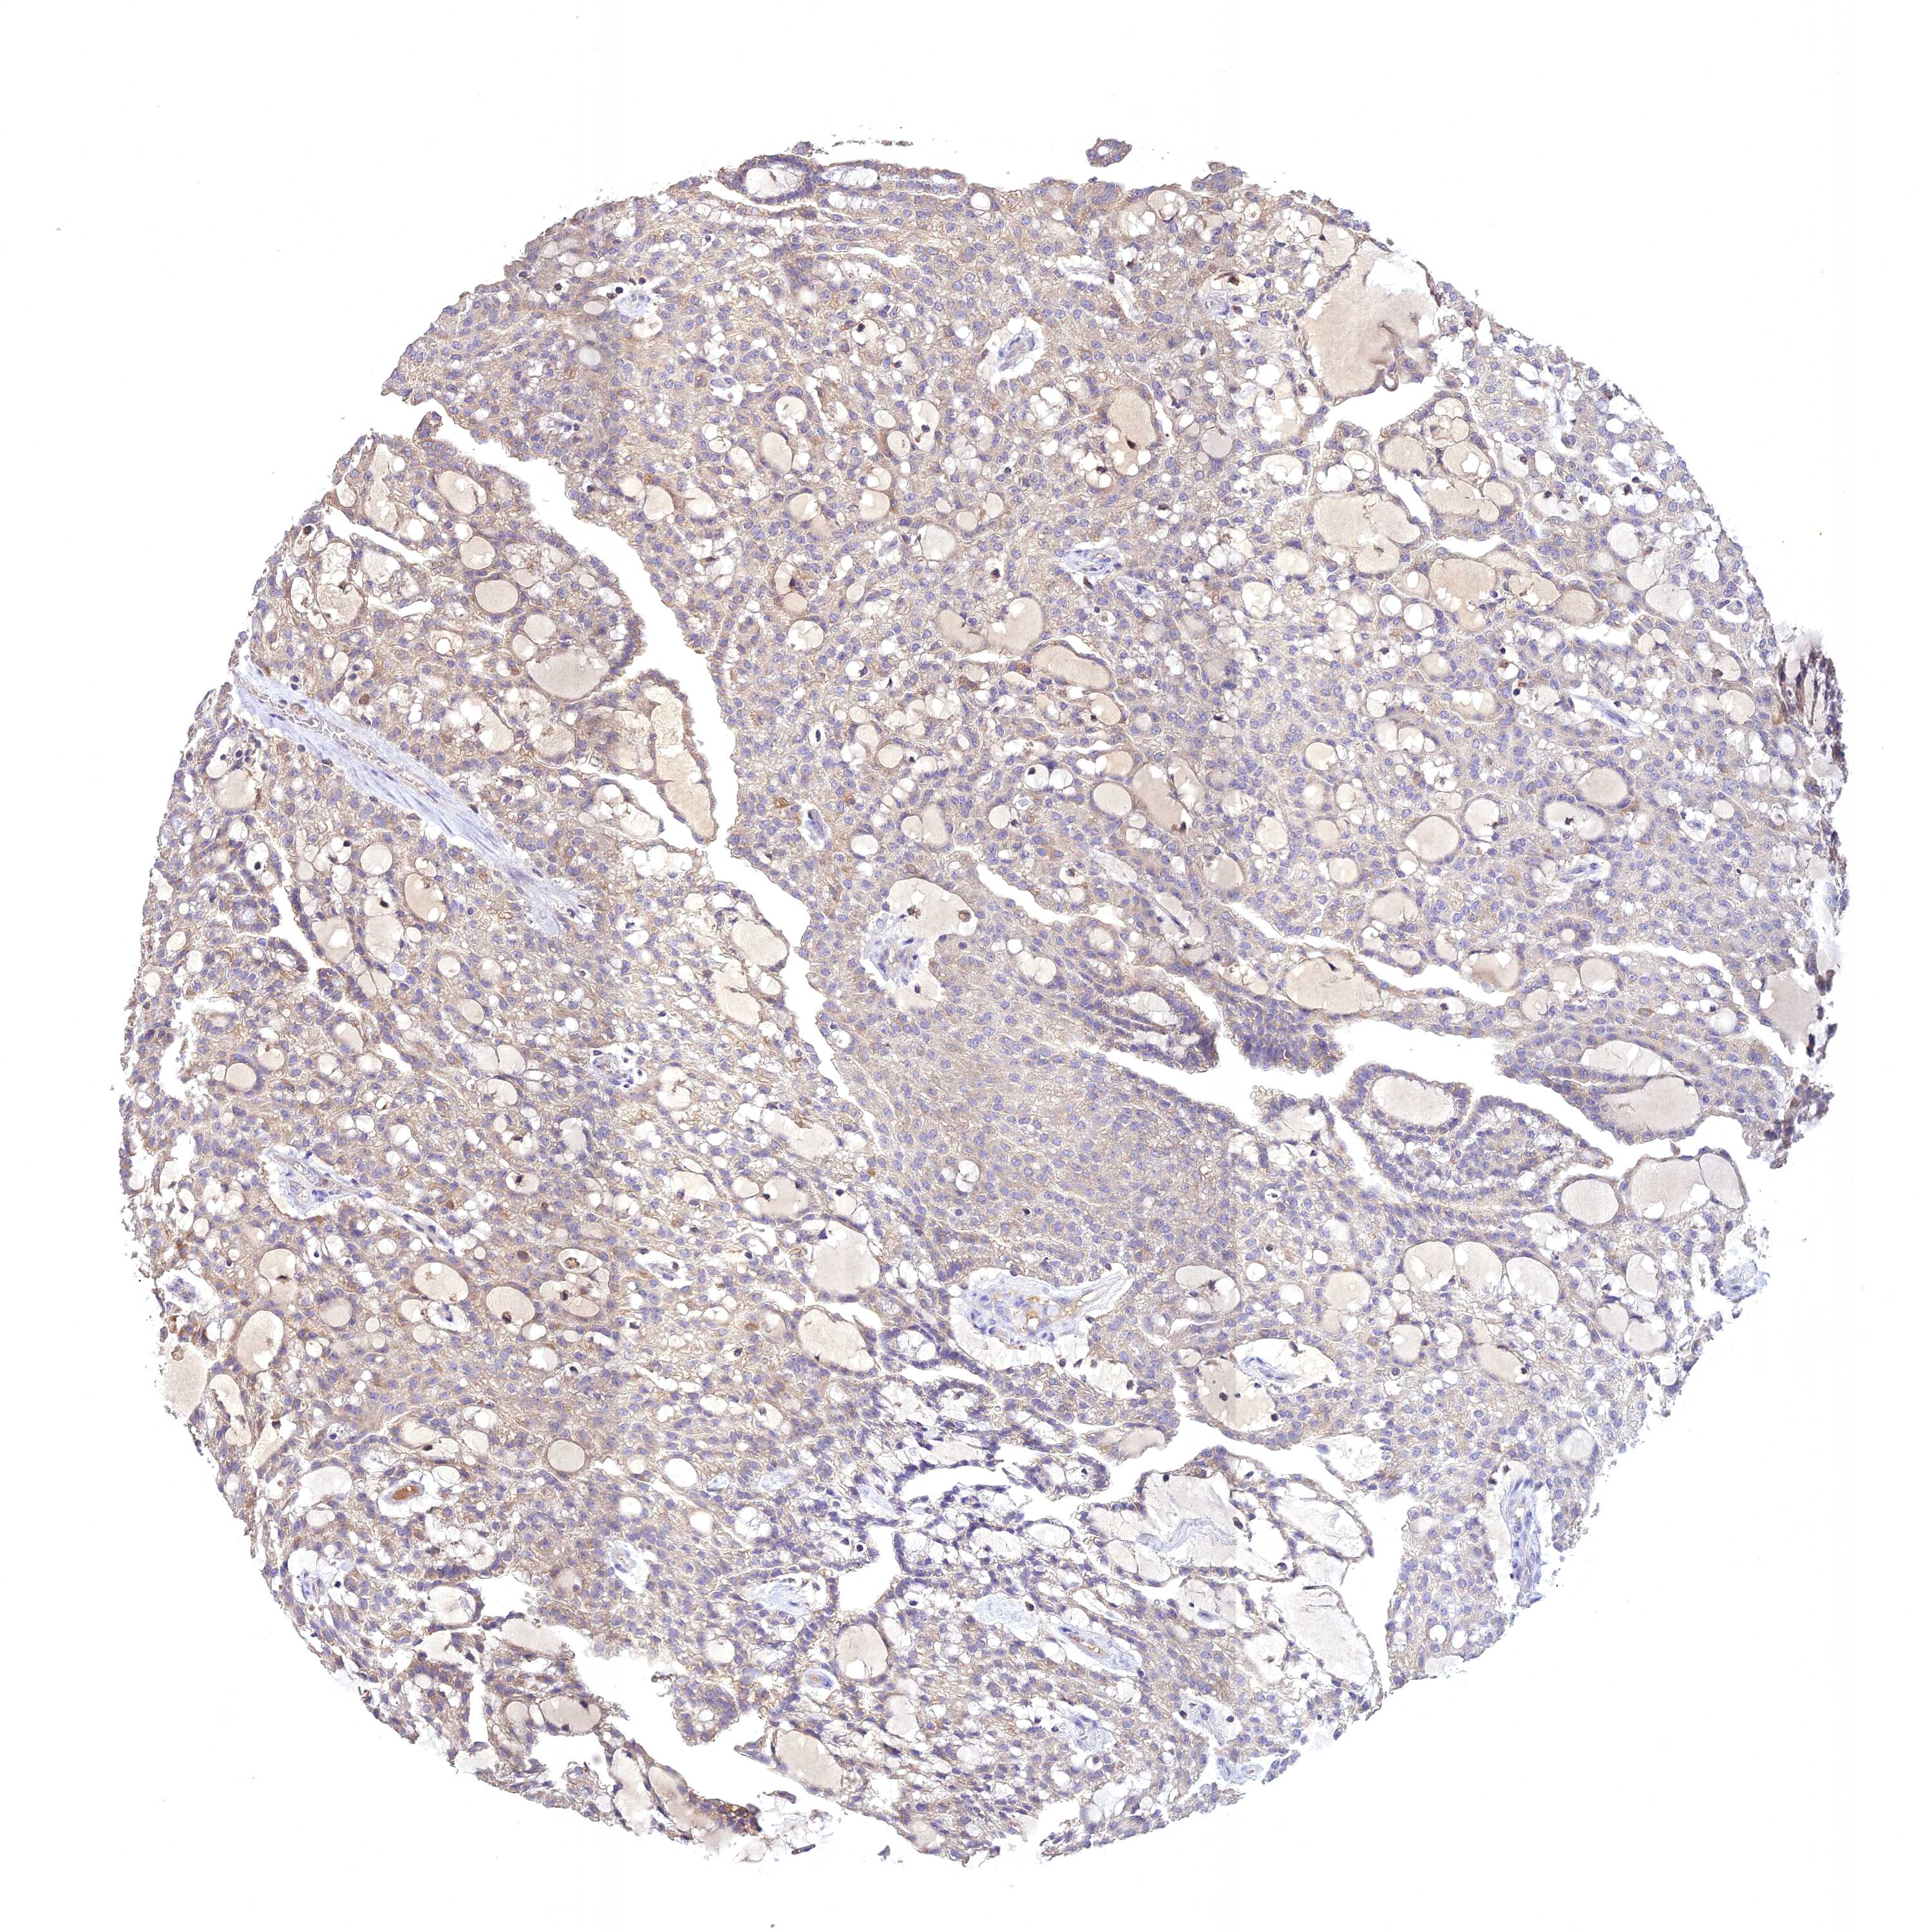

CANCER RENAL CANCER Show tissue menu

KICH TCGA KIRC TCGA KIRC VALIDATION KIRP TCGA PROTEIN RCC CPTAC PROTEIN EXPRESSION